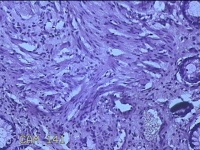

性别

男

年龄

40岁

临床诊断

混合痔

一般病史

反复肛门肿物突出15年。

标本名称

肛门肿物

大体所见

灰白暗红色肿物0.7x0.5x0.2cm一个,表面糜烂。

脱水、透明,浸蜡、脱蜡效果不佳,制片质量差。